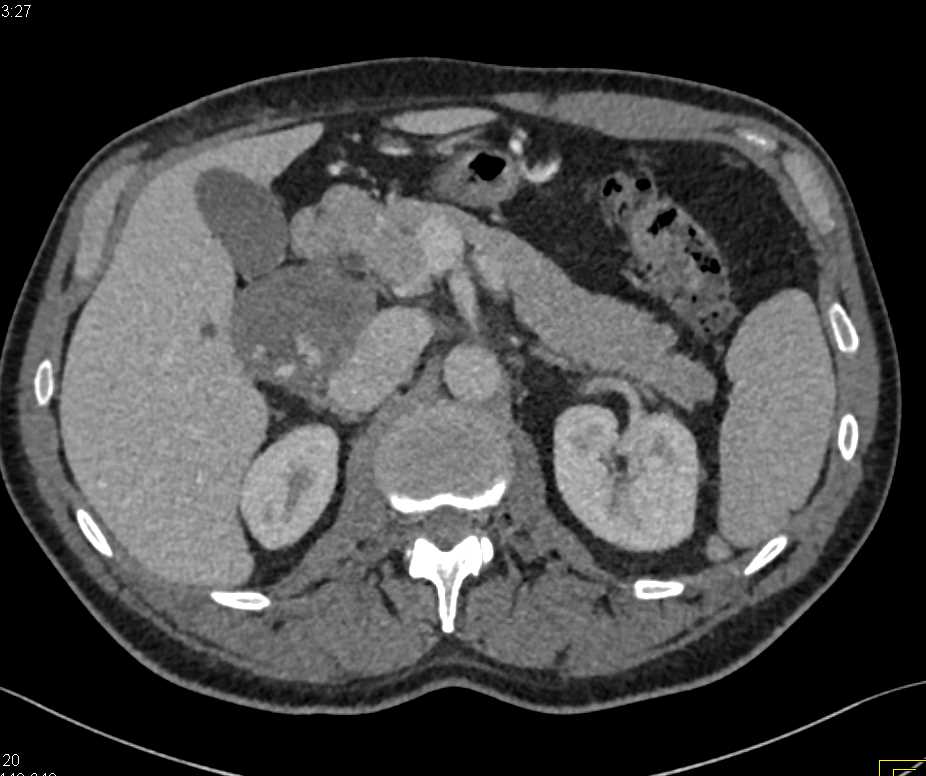

Poor Right Sided Heart Function with Dilated Inferior Vena Cava (IVC) and Hepatic Veins